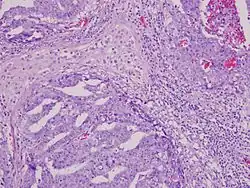

The differential diagnosis of testicular cancer requires examining the histology of tissue obtained from an inguinal orchiectomy—that is, surgical excision of the entire testis along with attached structures (epididymis and spermatic cord). A biopsy should not be performed, as it raises the risk of spreading cancer cells into the scrotum.[28]

Although testicular cancer can be derived from any cell type found in the testicles, more than 95% of testicular cancers are germ cell tumors (GCTs). Most of the remaining 5% are sex cord–gonadal stromal tumours derived from Leydig cells or Sertoli cells. A correct diagnosis is necessary to ensure the most effective and appropriate treatment. To some extent, this can be done via blood tests for tumor markers, but definitive diagnosis requires examination of the histology of a specimen by a pathologist. Testicular tumors are best classified by radical inguinal orchiectomy, which allows for histologic evaluation of the whole testicle and provides local tumor control.[39]